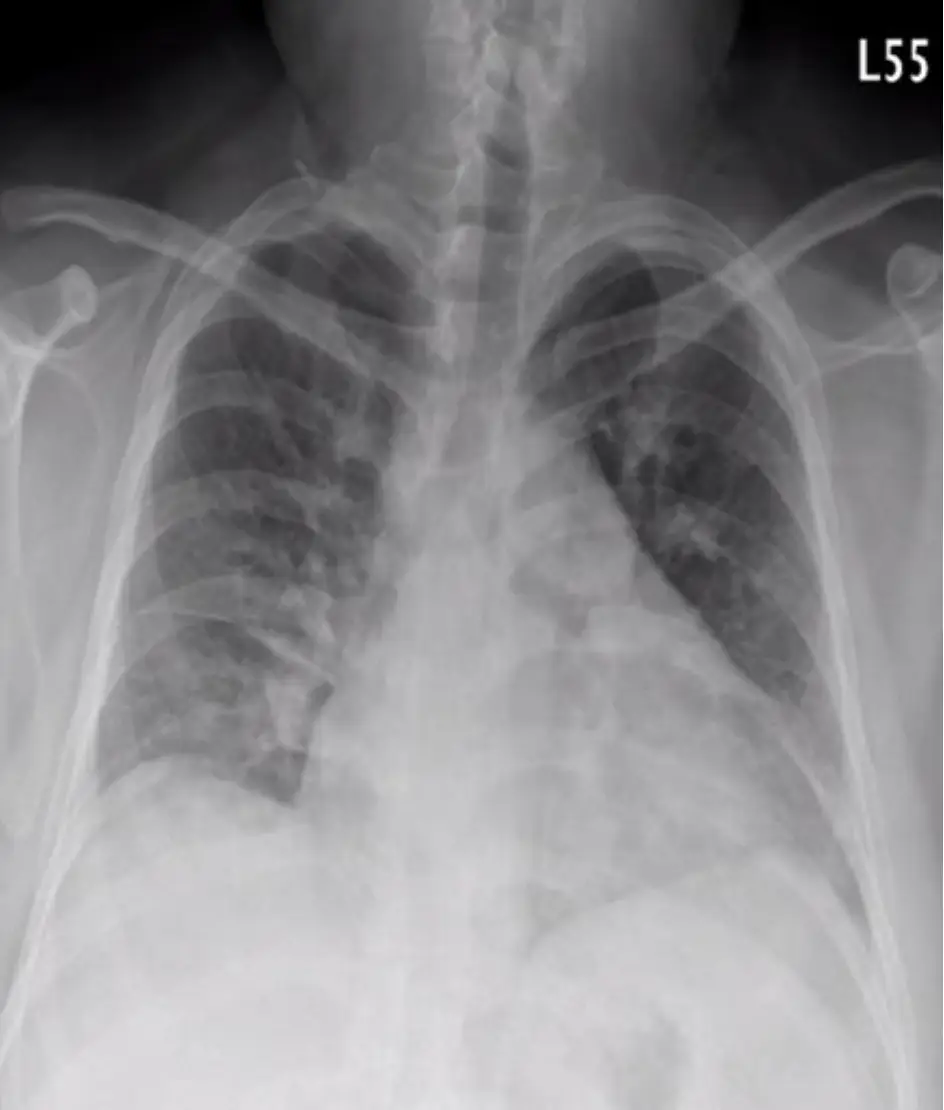

40歲企業主管因有心悸及呼吸困難有一個星期之久,乃前往A院求診,認定是上呼吸道感染,但處置無效,三天後至B院。病人在2009年診斷突發性上心室快跳,且有多年肥胖(BMI=41.5 Kg/m²) 。理學檢查: BP: 156/91 mmHg, HR:141/min, RR:28/min, Temp: 36.90℃, SpO2: 97%,無貧血,頸靜脈正常,甲狀 腺未有異常,胸部有混濁呼吸聲,心臟稍大,不正常律動,未有S3及心雜音,肝脾不大,無腹水,雙下 肢微腫時,心電圖、胸部X-光及胸部電腦斷層如圖。其生化及血液氣體檢驗如表。請問下列何項診斷最 正確? 圖片描述 圖片描述 圖片描述 圖片描述 圖片描述

2. 胸部 X-ray

• 心臟大小無明顯擴大,兩肺紋理部分區域變少並呈相對透明 (Westermark sign),右下葉近胸膜處淡淡楔形實變陰影,符合 Hampton hump。雖敏感度低,但在臨床情境下具高度提示性。